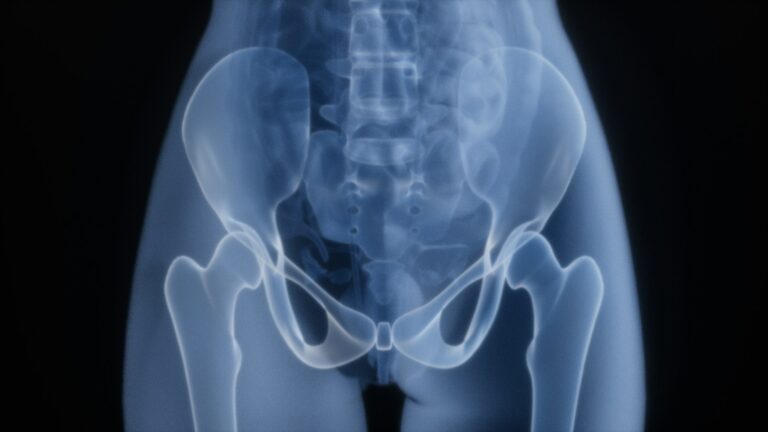

Conditions We TreatWe offer comprehensive diagnosis and treatment for a full spectrum of conditions—from neck and back pain to neurological and mental health disorders.

Why Choose Dr. Nasiek?Dr. Dariusz Nasiek, MD is a Triple Board-Certified pain management specialist with over 35 years of medical experience and more than 20 years working hands-on in the operating room. He has performed thousands of interventional procedures to treat spine, joint, and nerve-related pain caused by injury, trauma, or degeneration.

We offer cutting-edge procedures tailored to your condition, including minimally invasive options that promote faster recovery.

Dr. Dariusz Nasiek, MD, specializes in advanced, minimally invasive pain treatments that target spine...